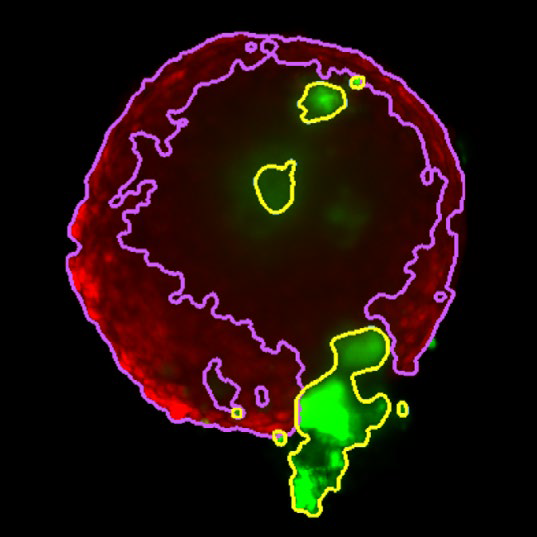

Figure 3. Z slice of the tumor microtissue treated with 0.05 % DMSO - tumor (yellow region) and fibroblast (purple region) are recognized separately in 3D. Image Credit: Yokogawa Life Science

Figure 4. Z slice of the tumor microtissue treated with 5 μM Lapatinib - tumor (yellow region) is decreased significantly compared to the one treated with 0.005 % DMSO. Image Credit: Yokogawa Life Science

Outcome

Tumor spheroids were created by seeding an Akura™ 384 plate with a monodispersed mixture of GFP-expressing NCI-N87 (gastric carcinoma) and RFP-expressing NIH3T3-L1 (murine fibroblast) cells, which spontaneously formed spheroids through scaffold-free self-assembly over several days. After spheroid formation, selected wells containing tumor spheroids were treated with DMSO at 0.05, 0.5, or 5.0 μM Lapatinib for six days. The images were analyzed in 3D, with NCI-N87-GFP (tumor) and NIH-RFP (fibroblast) identified separately, and the volume of each spheroid measured.